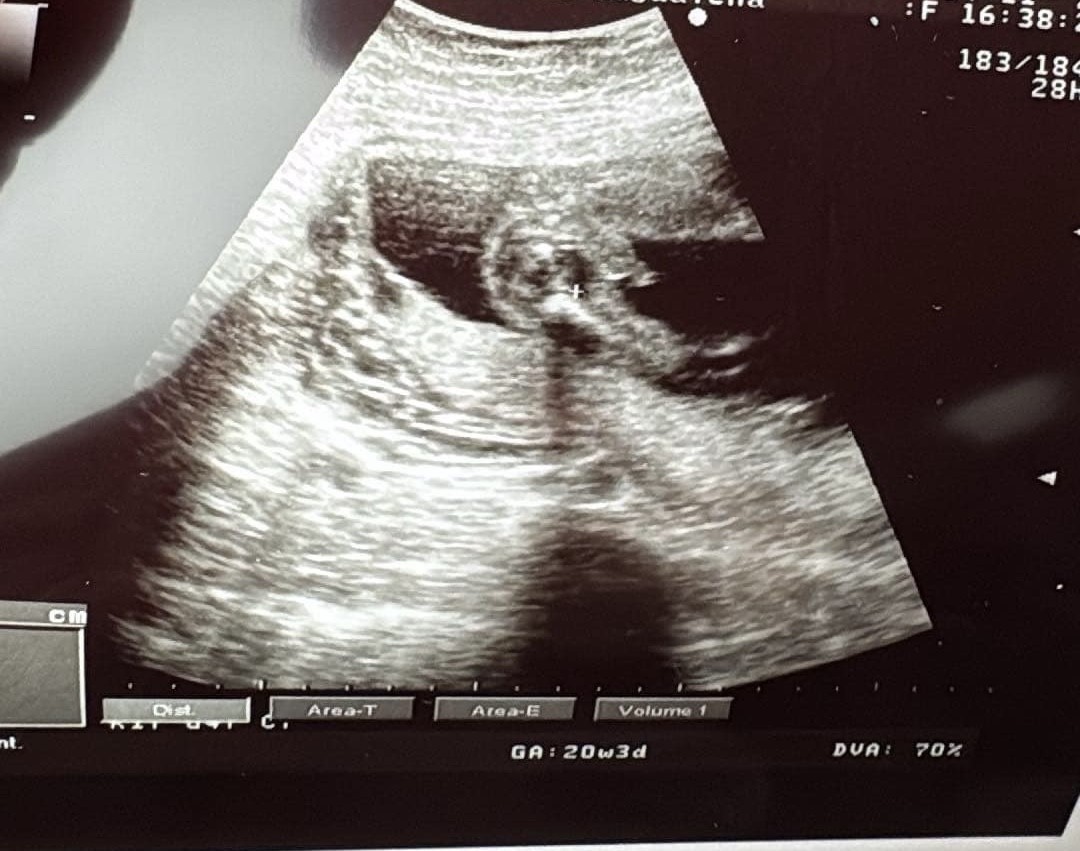

Dziewczyny jak mysliscie chłopczyk czy dziewczynka ?

Po czym rozpoznajecie ?Chłopiec!![]()

widać nóżki a pomiędzy męski narząd plciowy ewidentniePo czym rozpoznajecie ?